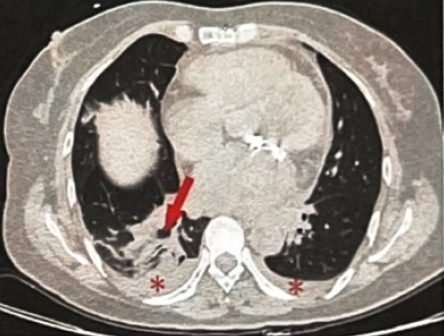

◆入院超声心动图:二尖瓣置换+三尖瓣成形术后:人工瓣功能未见明显异常(图2)。

(4).png)

二尖瓣为人工瓣,瓣体呈金属强回声,未见明显瓣周漏。三尖瓣轻度反流。左心室舒张末内径(LVEDD)4.7cm,左心室射血分数(LVEF)56%